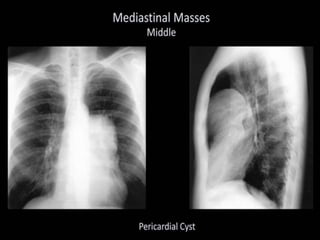

This document provides an overview of interpreting chest x-rays and identifies several key factors. It discusses the importance of inspiration, penetration, and rotation in obtaining a technically quality radiograph. It also outlines different views of chest x-rays including PA, AP, and lateral views. Finally, it identifies several anatomical structures that should be evaluated when interpreting a chest x-ray such as the lungs, heart, diaphragm, bones, and soft tissues.